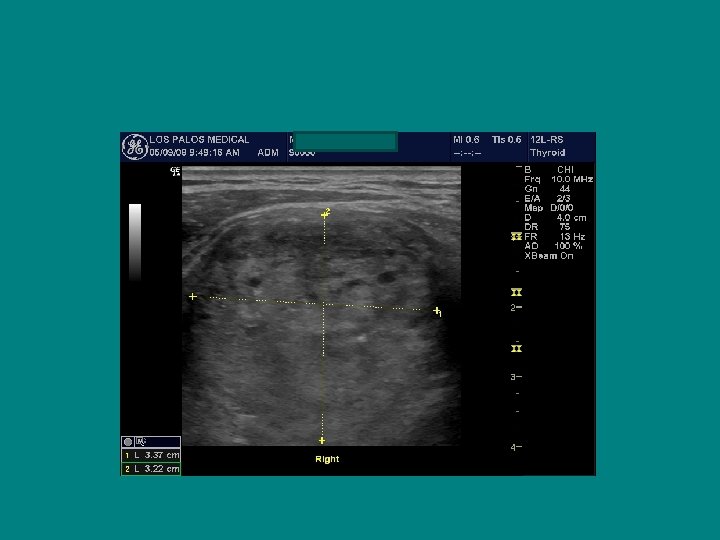

Right Left

• 30 YEAR OLD FEMALE WITH MULTI NODULAR GOITER DISCOVERED SEPT 2006 ANTI-TPO 154, ANTI TG AB-368 TSH 7. 36 • FNA CONSISTENT WITH WELL DIFFERENTIATED PAPILARY THYROID CANCER ON THE RIGHT • LEFT INDETERMINATE

SEARCH FOR RECURRENT/RESIDUAL DISEASE • HYPOECHOIC MASS, LIKELY LYMPH NODE • AP/T 0. 7 CM !!